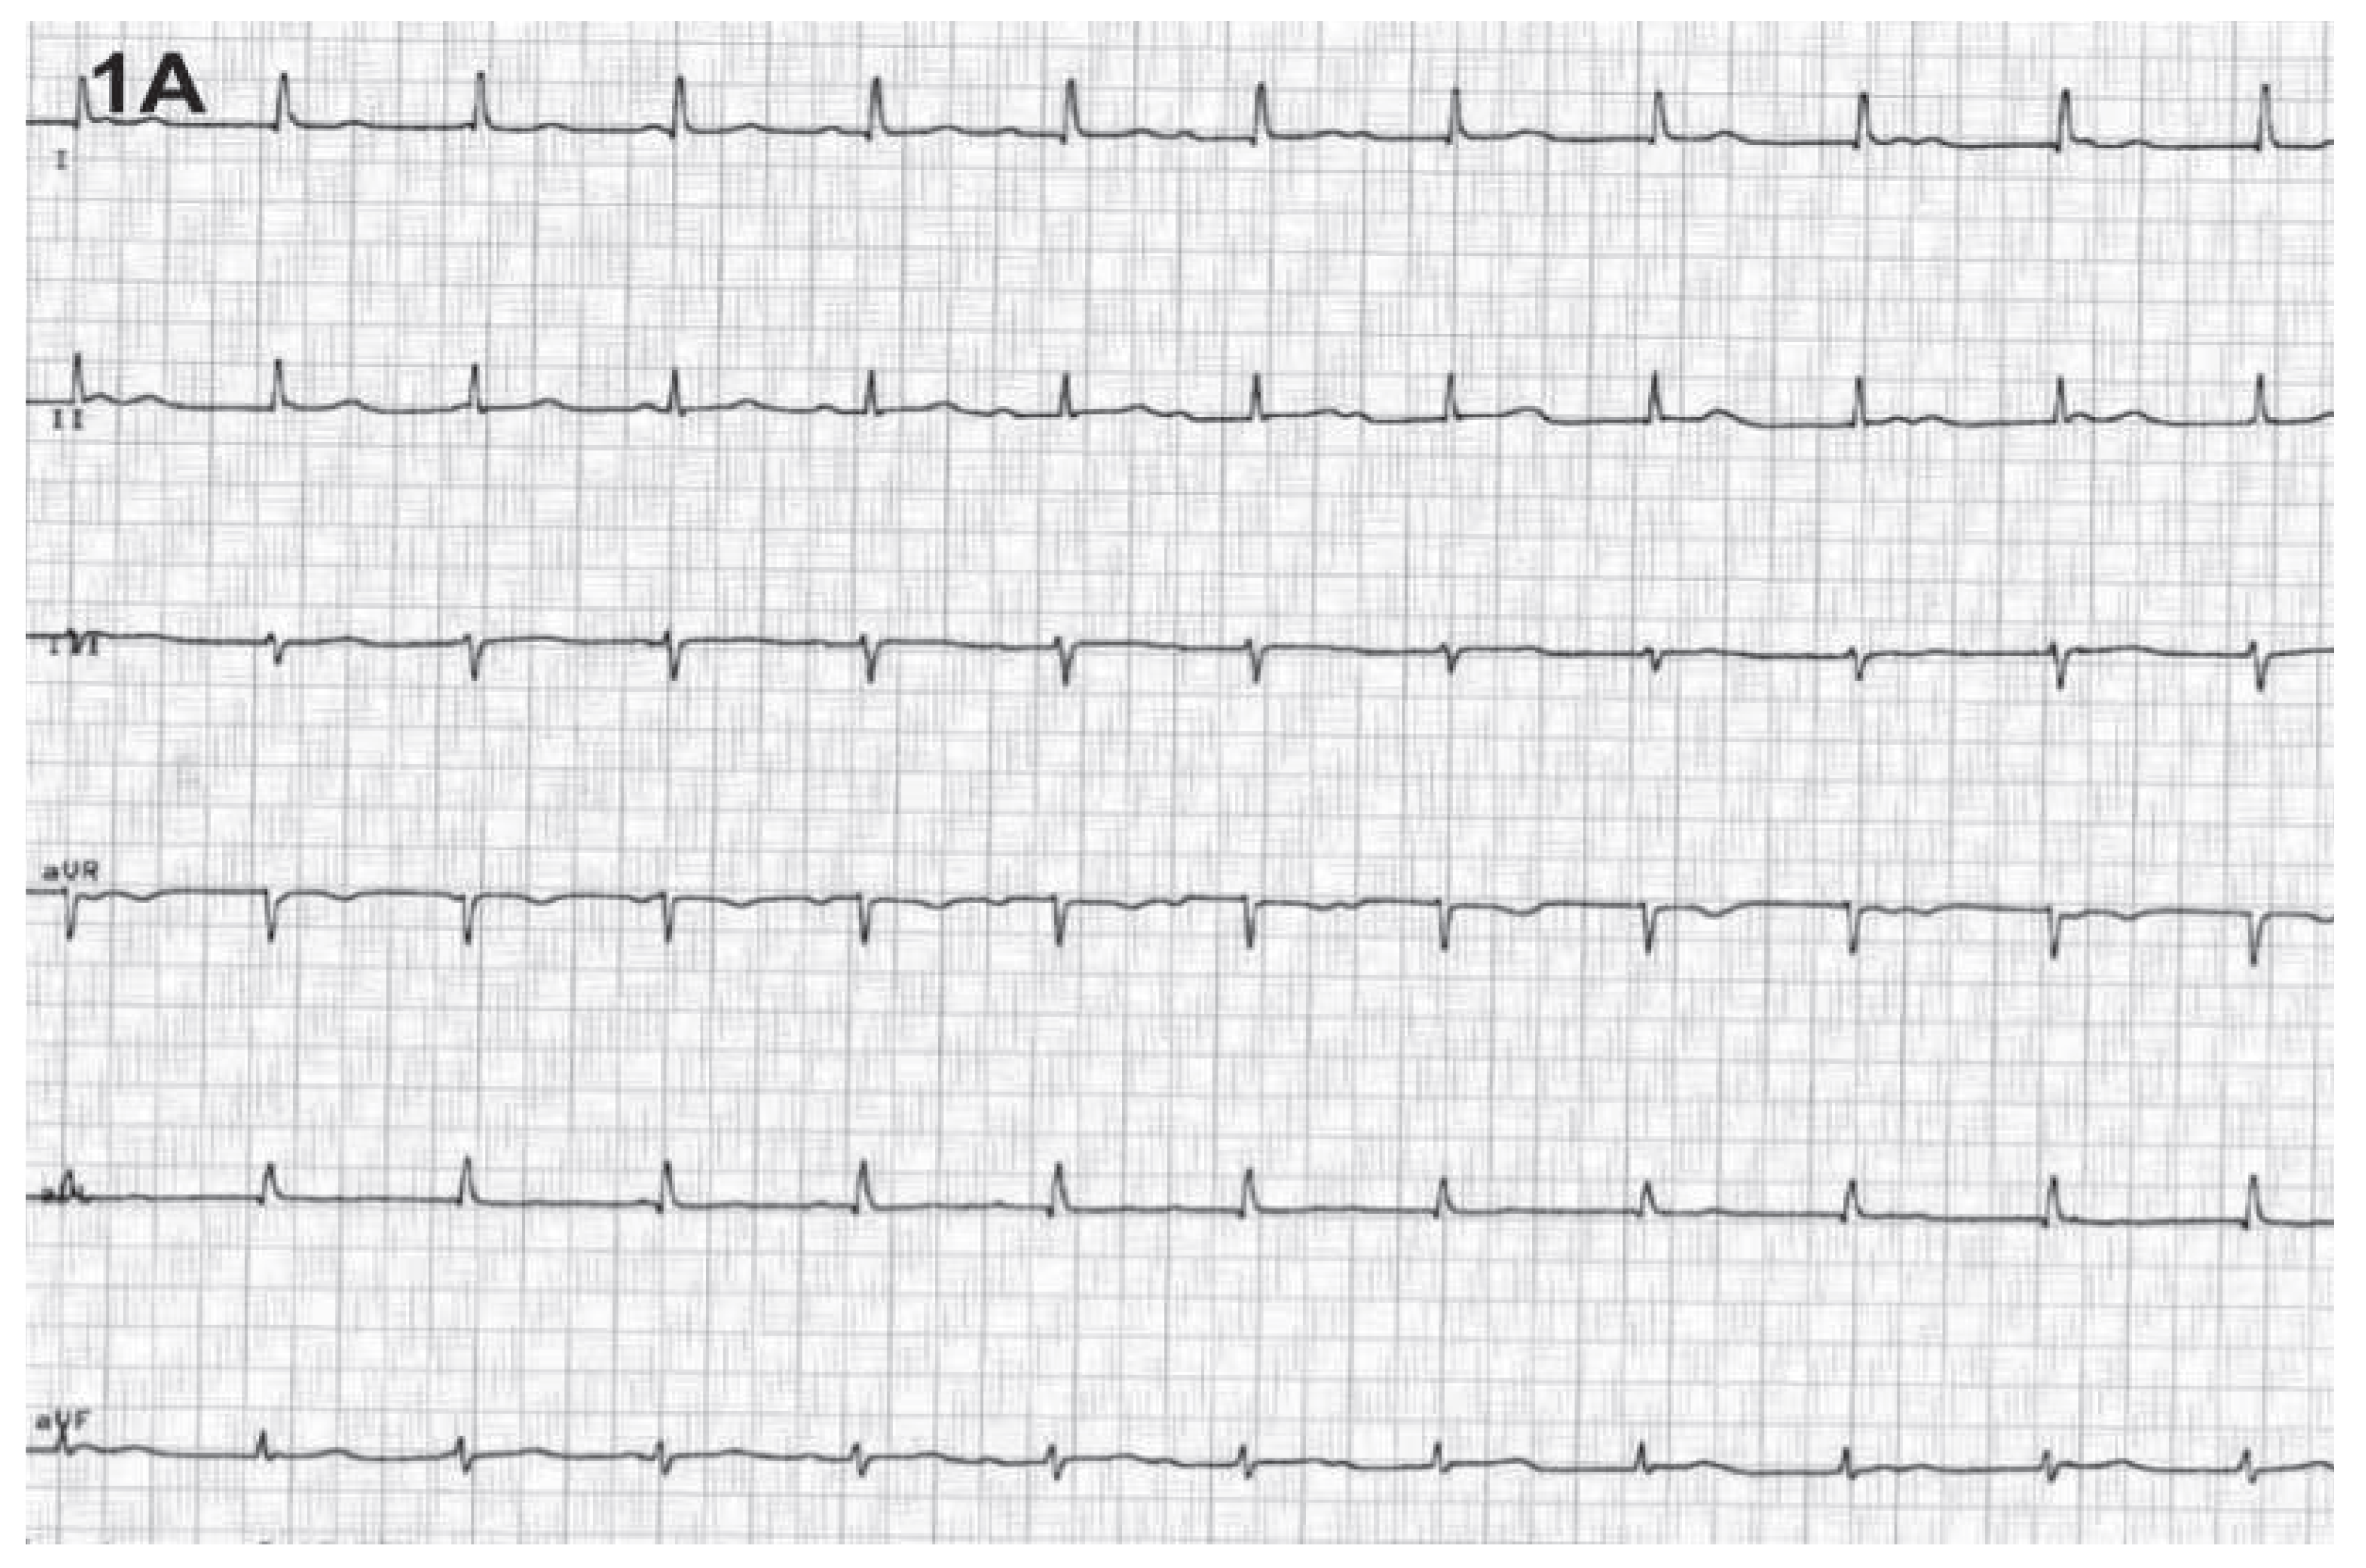

Cannon Wave “Equivalent” —A Clinical Sign Observed During Echocardiography